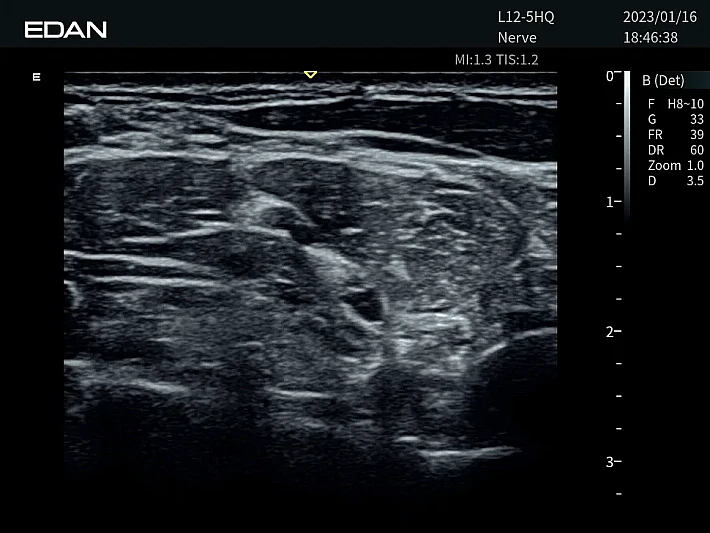

Медицинское оборудование и сервисное обслуживание